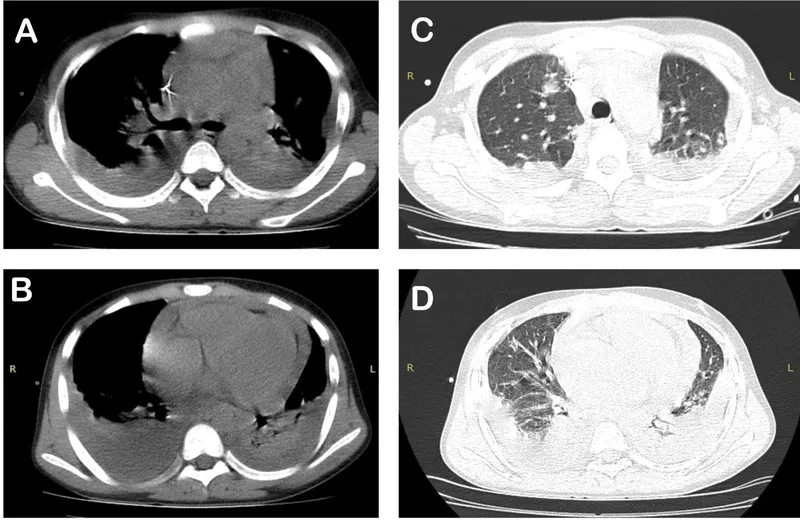

A visual guide to glanders disease symptoms

• Glanders disease symptoms vary based on the infection type, including cutaneous glanders (skin nodules), pulmonary glanders (cough), or septicemic glanders (fever).

What the symptoms of Glanders look like

Lesions showing the progression of glanders in humans